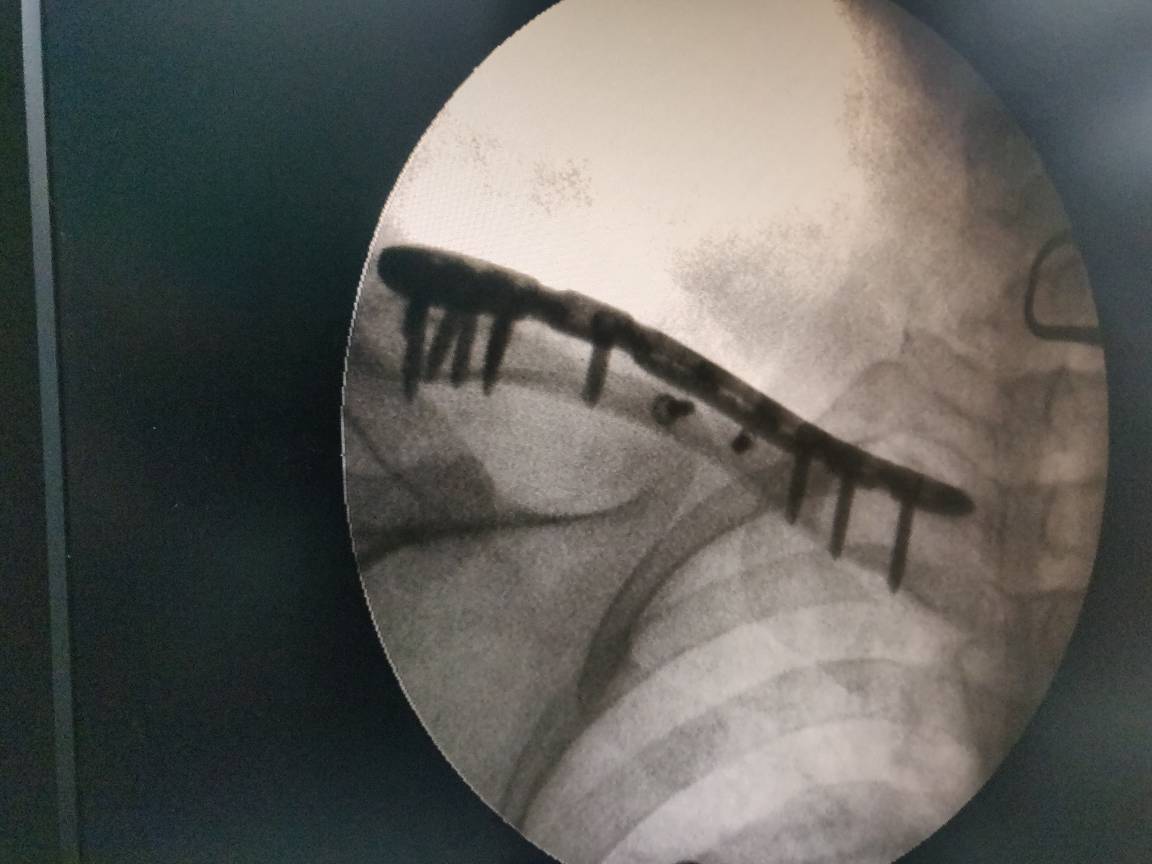

Best orthopedic surgeon in Aundh Clavicle fracture is one of common injury Best treatment is orif with plating Visit UNITY hospital for further information